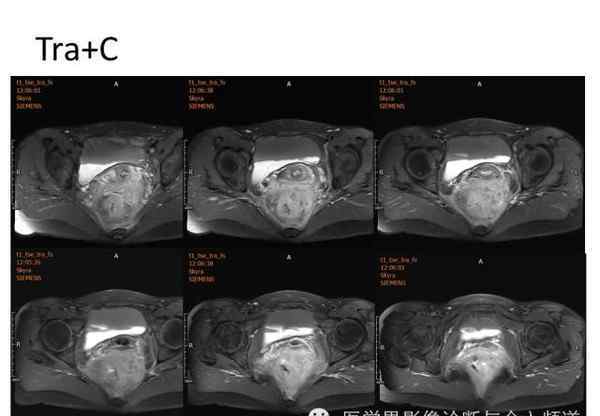

核磁共振平片扫描和增强扫描显示:

盆腔内可见弥漫性长T1长T2异常信号,FS-T2WI可见高信号,涉及直肠左前壁、直肠侧韧带和宫颈等。边界不清,盆腔可见条带状FS-T2WI高信号强度。注射钆喷酸葡胺后,病情明显加重。